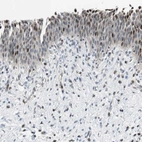

Immunohistochemical staining of human urinary bladder shows moderate nuclear positivity in urothelial cells.